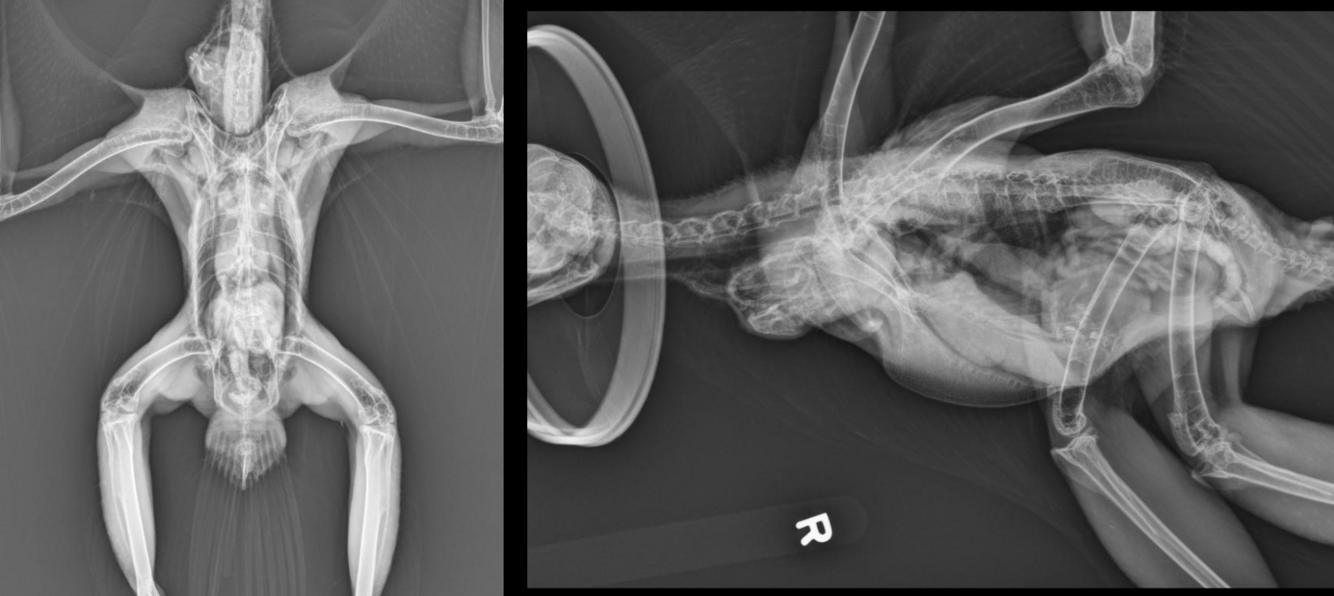

What are the parts of skeletal anatomy labelled in this image?

A

1: sternum

2: coracoid

3: clavicles/furcula

4: scapula

What can be assessed on a sedated VD view?

-symmetry of organs

-pectoral and pelvic girdle

-heart and liver silhouette

-caudal air sacs

What are the keys to taking a good VD view in birds?

-straight body position

-keel overlying spine

-shoulders symmetrical and level